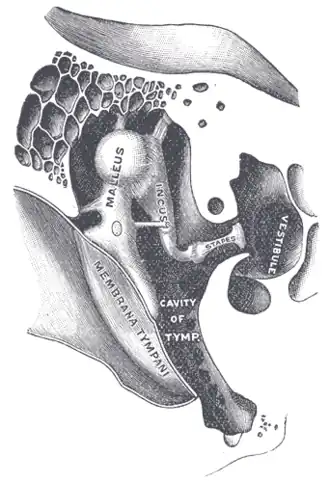

L'étrier ou stapès[1] est le plus interne des trois osselets de l'oreille. Il s’articule avec l'enclume (ou incus) et la fenêtre du vestibule.

Il est situé dans la cavité tympanique et se positionne horizontalement entre le processus lenticulaire de l'enclume et la fenêtre du vestibule.

Articulations

L'étrier s'articule avec l'enclume via une énarthrose. La surface articulaire arrondie de l'os lenticulaire va s'insérer dans la cavité glénoïdale de la tête de l'étrier. Ces deux surfaces sont recouvertes de cartilage, et l'articulation est maintenue par une capsule, tapissée de synoviale.

La platine de l'étrier s'articule à la fenêtre du vestibule par la syndesmose tympano-stapédiale. Elle comble partiellement la fenêtre du vestibule, et est reliée au bord de la fossette de la fenêtre du vestibule par le ligament annulaire du stapès.

Anatomie fonctionnelle

L'étrier est le dernier des trois osselets formant la chaine des osselets, dont le rôle est de transférer et d'amplifier la vibration sonore, du tympan à l'oreille interne. Il reçoit les vibrations de l'enclume, et va ainsi transmettre cette vibration aux liquides de l'oreille interne via la fenêtre du vestibule, dans laquelle s'insère sa base.